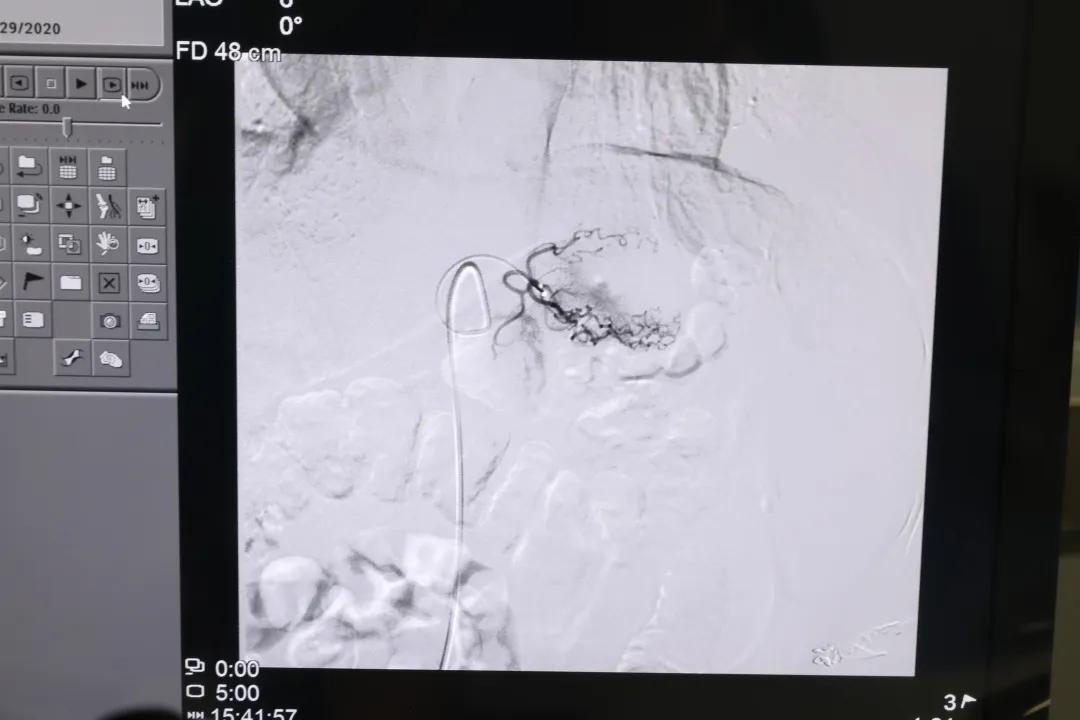

介入室里,宁阳县第一人民医院胸外科医生许彪和放射科介入科主任宁连金注视着眼前的屏幕,随着药物的注入,造影显示,肿瘤周围的末梢血运已经消失,严密观察之后,患者被送回病房。

许彪介绍说,肿瘤灌注化疗+栓塞治疗是运用DSA(数字减影技术)对患者肿瘤病灶进行精准定位,通过导管注射化疗药物,使药物直接作用于肿瘤细胞,对肿瘤组织进行破坏,杀死肿瘤细胞;同时,用药物阻断肿瘤的血液供应,使肿瘤组织无法再汲取营养,简单说,就是给肿瘤“断粮”,从而阻止肿瘤细胞的生长,甚至可以令其坏死凋亡,以达到控制肿瘤生长,使肿瘤缩小的目的。

放射介入科主任宁连金介绍说,DSA可视动脉介入灌注栓塞术是采用微创治疗的方式,仅在大腿根部处有一个2-3毫米的穿刺创口;将高浓度的药物直接作用于局部,发挥最大的抗肿瘤作用。而且对全身毒副作用小,能最大限度保护*体器人官**,绝大部分患者可耐受。适于多种肿瘤,如肝癌、肺癌、乳腺癌、胰腺癌、胃癌、肠癌、骨肉瘤等。